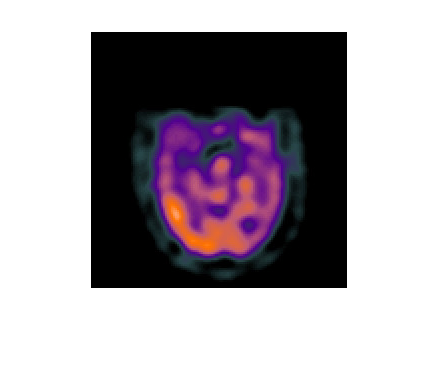

基于拉普拉斯重分解的多模态医学图像融合,核心是通过多尺度、精细化的拉普拉斯重分解拆分图像的低频结构与高频细节,再针对医学图像的临床需求(如结构完整性、病灶凸显性)设计分层融合规则,实现 CT/MRI、PET/CT 等多模态图像的信息互补,为临床诊断与手术规划提供更全面的视觉支撑。该方法突破传统拉普拉斯金字塔 “单一尺度分解” 的局限,通过重分解增强细节分离能力,兼顾融合精度与医学实用性。

多模态医学图像的融合目标是互补不同模态的优势信息:

PET 图像:反映代谢活性(如肿瘤恶性程度),但空间分辨率低、结构模糊。融合需实现 “结构 + 功能 + 细节” 的三维互补,确保医生能同时观察解剖结构与病理特征。

模态差异大:不同模态的灰度分布、噪声特性、信息密度差异显著(如 CT 灰度范围宽,PET 灰度集中);